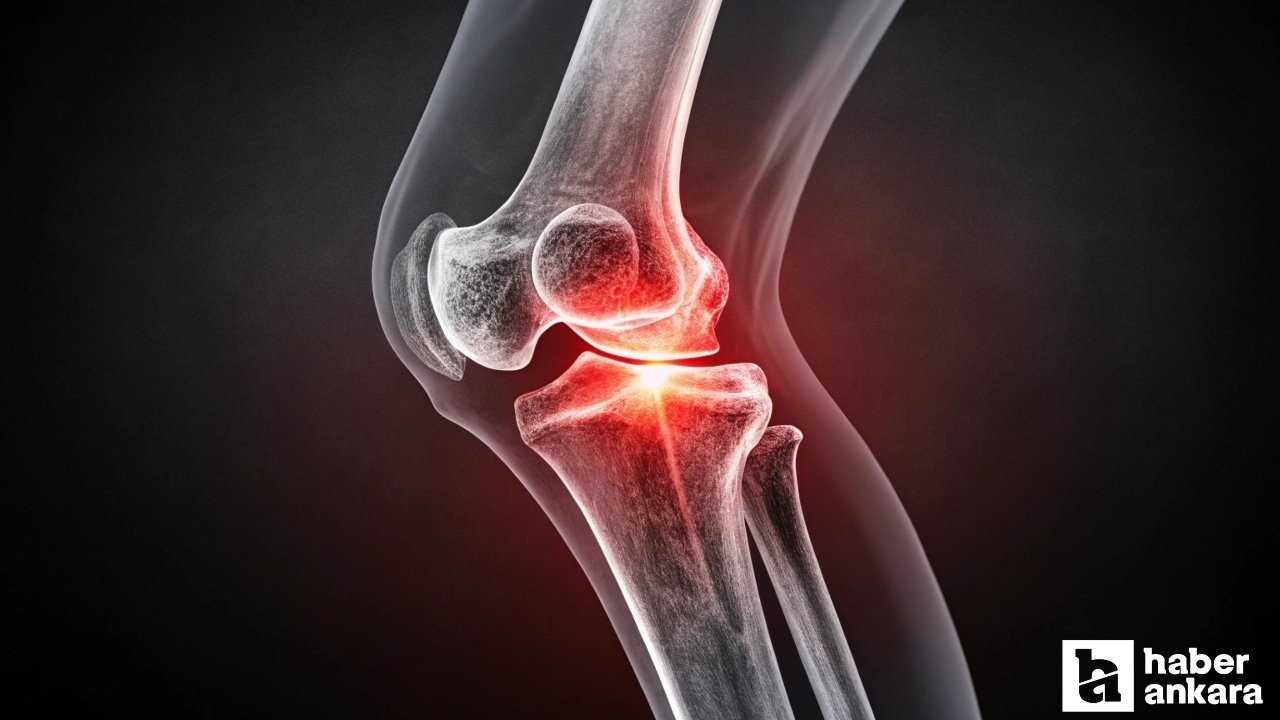

Dizde 2 haftadan uzun süren ağrısı olanlara uzmanlardan dikkat çeken uyarı

Uzmanlar uzun süredir süren diz ağrılarına karşın uyarıda bulundu. Konuya ilişkin açıklama yapan Ortopedi ve Travmatoloji Bölümü'nden Doç. Dr. Murat Köken, diz ağrılarının her yaşta görülebileceğini aktardı.